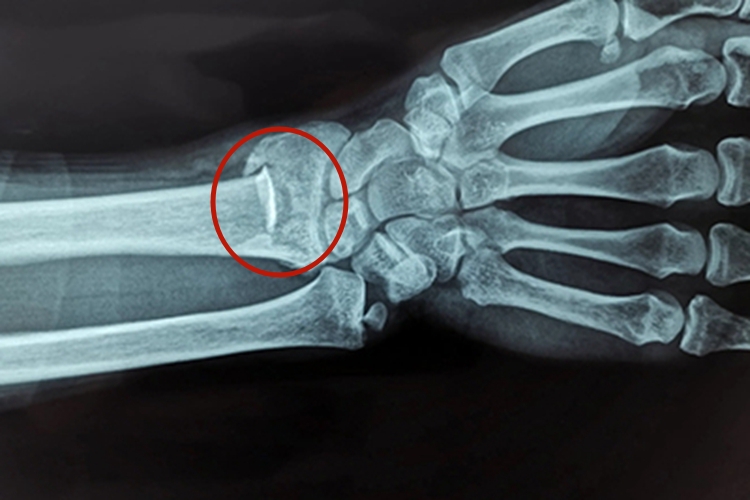

X线片可见桡骨远端骨折块向背侧移位;桡骨远端骨折块向桡侧移位;桡骨远端骨折块向掌侧成角;桡骨远端短缩,骨折远端背侧骨皮质与近端嵌插;桡骨远端骨折块旋后。上述表现组合成为典型的餐叉样畸形,使正常掌倾角及尺偏角减少,或呈负角度。